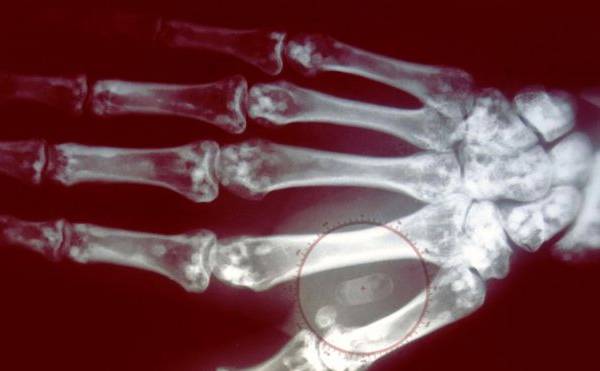

microchip

Image caption Los microchips tienen el tamaño de un grano de arroz.

microchip implantado en la mano

Image caption El microchip se coloca debajo de la piel, entre los dedos índice y pulgar.